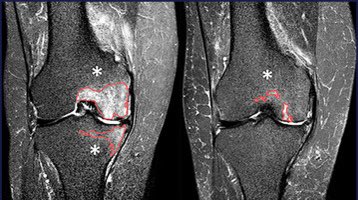

"CBCT is a powerful adjunct in GAE to rapidly identify target vessels for embolization & potentially decrease the risk of nontarget embolization," conclude researchers from UCLA Radiology & UCLA in CVIR Journal. pubmed.ncbi.nlm.nih.gov/36949185/